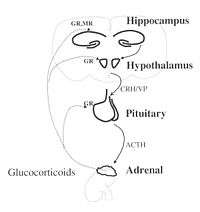

Hypothalamic-pituitary-adrenal (HPA) axis

The HPA axis is a multi-step biochemical pathway where information is transmitted from one area of the body to the next via chemical messengers. Each step in this pathway, as in many biochemical pathways, not only passes information along to stimulate the next region but also receives feedback from messengers produced later in the pathway to either enhance or suppress earlier steps in the pathway – this is one way a biochemical pathway can regulate itself, via a feedback mechanism.

When the hypothalamus receives signals from one of its many inputs (e.g., cerebral cortex, limbic system, visceral organs) about conditions that deviate from an ideal homeostatic state (e.g., alarming sensory stimulus, emotionally charged event, energy deficiency), this can be interpreted as the initiation step of the stress-response cascade. The hypothalamus is stimulated by its inputs and then proceeds to secrete corticotropin-releasing hormones. This hormone is transported to its target, the pituitary gland, via the hypophyseal portal system (short blood vessels system), to which it binds and causes the pituitary gland to, in turn, secrete its own messenger, adrenocorticotropic hormone, systemically into the body's blood stream. When adrenocorticotropic hormone reaches and binds to its target, the adrenal gland, the adrenal gland in turn releases the final key messenger in the cascade, cortisol. Cortisol, once released, has widespread effects in the body. During an alarming situation in which a threat is detected and signaled to the hypothalamus from primary sensory and limbic structures, cortisol is one way the brain instructs the body to attempt to regain homeostasis – by redistributing energy (glucose) to areas of the body that need it most, that is, toward critical organs (the heart, the brain) and away from digestive and reproductive organs, during a potentially harmful situation in an attempt to overcome the challenge at hand.

After enough cortisol has been secreted to best restore homeostasis and the body's stressor is no longer present or the threat is no longer perceived, the heightened levels of cortisol in the body's blood stream eventually circulate to the pituitary gland and hypothalamus to which cortisol can bind and inhibit, essentially turning off the HPA-axis' stress-response cascade via feedback inhibition. This prevents additional cortisol from being released. This is biologically identified as a normal, healthy stress mechanism in response to a situation or stressor – a biological coping mechanism for a threat to homeostasis.

It is when the body's HPA-axis cannot overcome a challenge and/or is chronically exposed to a threat that this system becomes overtaxed and can be harmful to the body and brain. A second major effect of cortisol is to suppress the body's immune system during a stressful situation, again, for the purpose of redistributing metabolic resources primarily to fight-or-flight organs. While not a major risk to the body if only for a short period of time, if under chronic stress, the body becomes exceptionally vulnerable to immune system attacks. This is a biologically negative consequence of an exposure to a severe stressor and can be interpreted as stress in and of itself – a detrimental inability of biological mechanisms to effectively adapt to the changes in homeostasis.